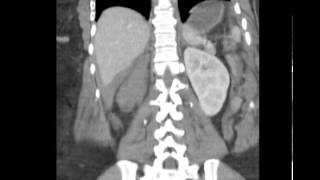

Blunt Abdominal Trauma Part 4 Renal Injury